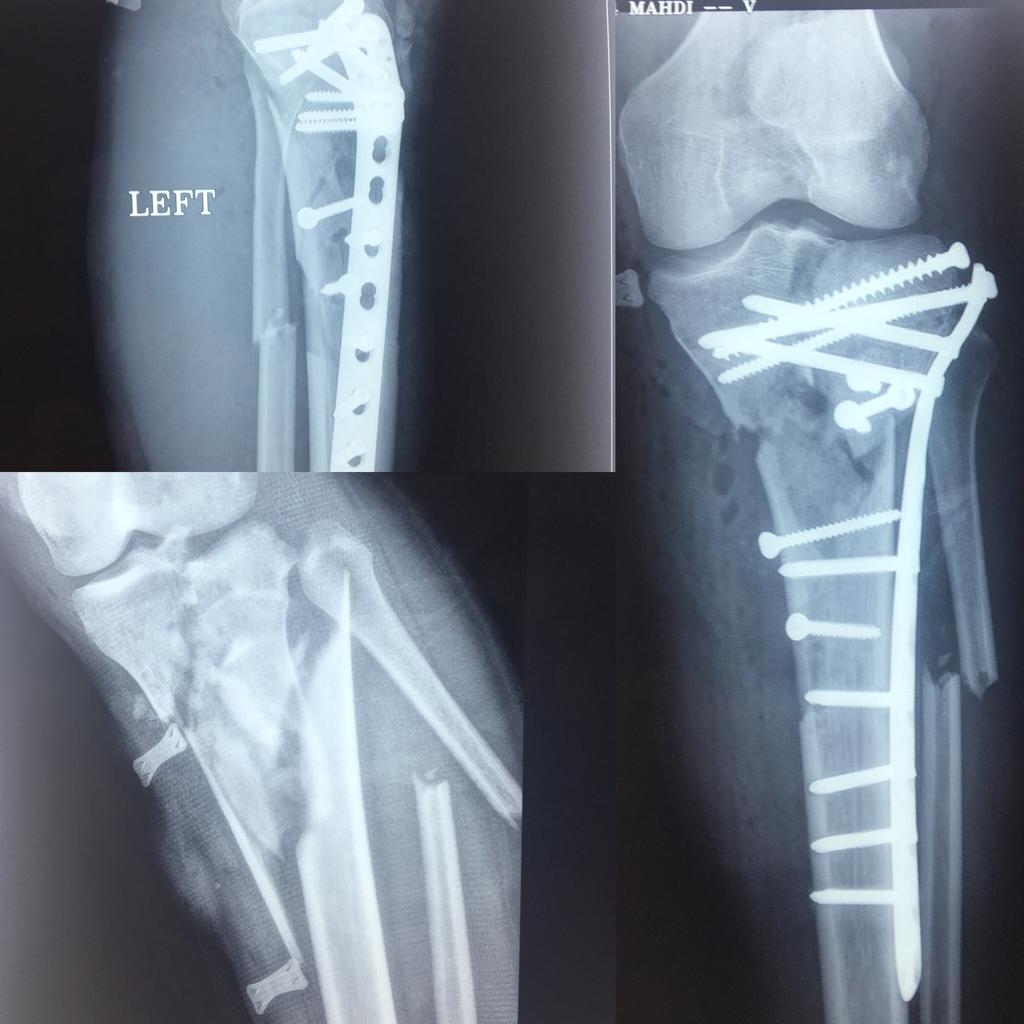

اقای 21 ساله با شکستگی له شده ی ساق و زانو که جراحی شد و بهبودی کاملاقای 50 ساله با قطع شدگی و له شدگی مچ پاله شدگی و قطع مچ پا6 ماه پس از جراحی ترمیمی و پیوندشکستگی مفصل ران و فمورجراحی فیکساسیون

شکستگی خرد شده ی مچ پاجراحی شکستگی مچ پا و بازسازی کامل مفصلشکستگی قدیمی پاشنه که جراحی شده بود و به شکل بدی جوش خورده بودبازسازی مجدد پاشنه و بهبودی بیماراقای 25 ساله با شکستگی کاسه ی لگن و ساق همزمان

اقای 25 ساله با شکستگی و تروما ی همزمان کاسه لگن و ساق که جراحی و بهبودی کامل